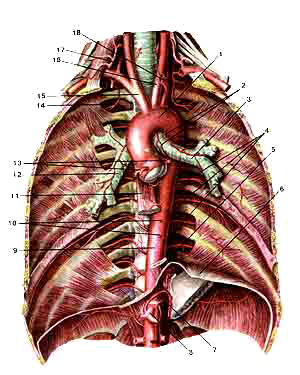

Грудная часть аорты (aorta thoracica) и ее ветви

Вид спереди. Легкие, сердце и другие внутренние органы, расположенные в грузной полости, удалены.

1-дуга аорты;

2-бронхиальные ветви;

3-левый главный бронх;

4-задние межреберные артерии;

5-пищевод (отрезан);

6-диафрагма;

7-нижняя диафрагмальная артерия;

8-чревный ствол;

9-фудная часть аорты;

10-пищеводные ветви;

11-пищевод (отрезан);

12-правый главный бронх;

13-венечные артерии (сердца);

14-самая верхняя межреберная артерия;

15-плечеголовной ствол;

16-левая общая сонная артерия;

17-правая позвоночная артерия;

18-левая подключичная артерия (отрезана и отвернута вправо).